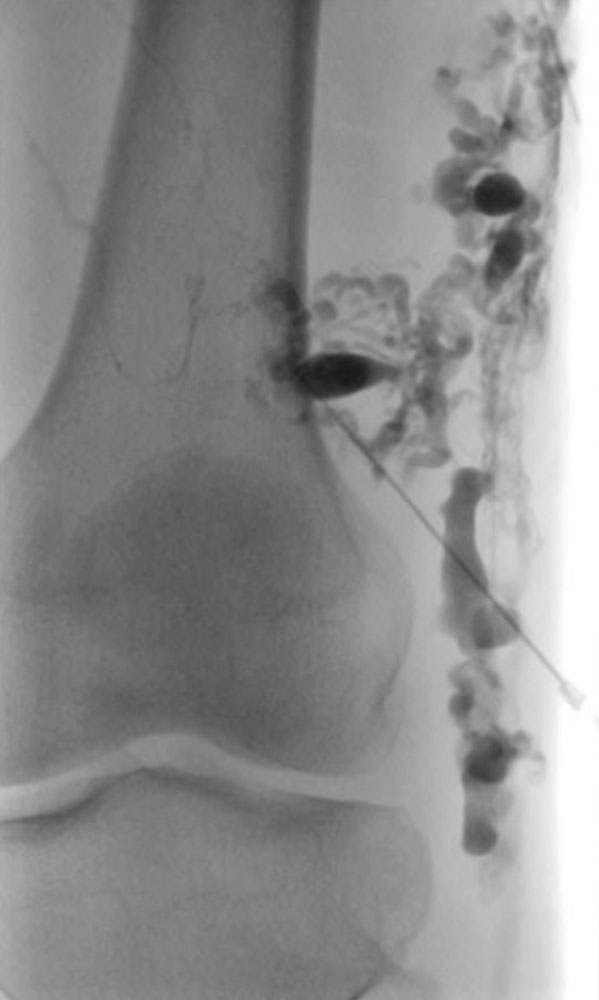

Bei einigen Patientinnen mit bisher unbehandelten oder nicht suffizient behandelten venösen Malformationen, bei denen eine Verbindung ins tiefe Leitvenensystem vorliegt („Kommunikationsvene“ oder Marginalvene) mit entsprechend erhöhter Gefahr einer Thrombose oder Thrombembolie, kann die Gefahr dieser Komplikation während der Schwangerschaft erhöht sein. Eine entsprechende Therapie vor der Schwangerschaft mit interventionellem oder operativem Verschluss dieser Kommunikationsvenen kann dieses Risiko erheblich vermindern oder ausschließen. Bei einzelnen Patientinnen kann zudem in Abwägung des individuellen Risiko-Nutzen-Verhältnisses während der Schwangerschaft eine längerdauernde Antikoagulation mit Heparin sinnvoll und notwendig sein. Daten liegen hier vor bei Patientinnen mit Klippel-Trénaunay-Syndrom (KTS), die allerdings keine ganz einheitlichen Ergebnisse zeigten. Einerseits bestand kein Unterschied in der Komplikationshäufigkeit zwischen schwangeren und nicht schwangeren Frauen mit Klippel-Trénaunay-Syndrom, dennoch war das Komplikationsrisiko im Vergleich zu Normalschwangeren erhöht, auch trat eine doppelt so hohe Rate an postpartalen Blutungen auf. In einer weiteren Studie, die KTS-Patientinnen mit nicht erkrankten Schwangeren verglich berichteten 43 % der KTS-Patientinnen über mehr Symptome während Schwangerschaft.